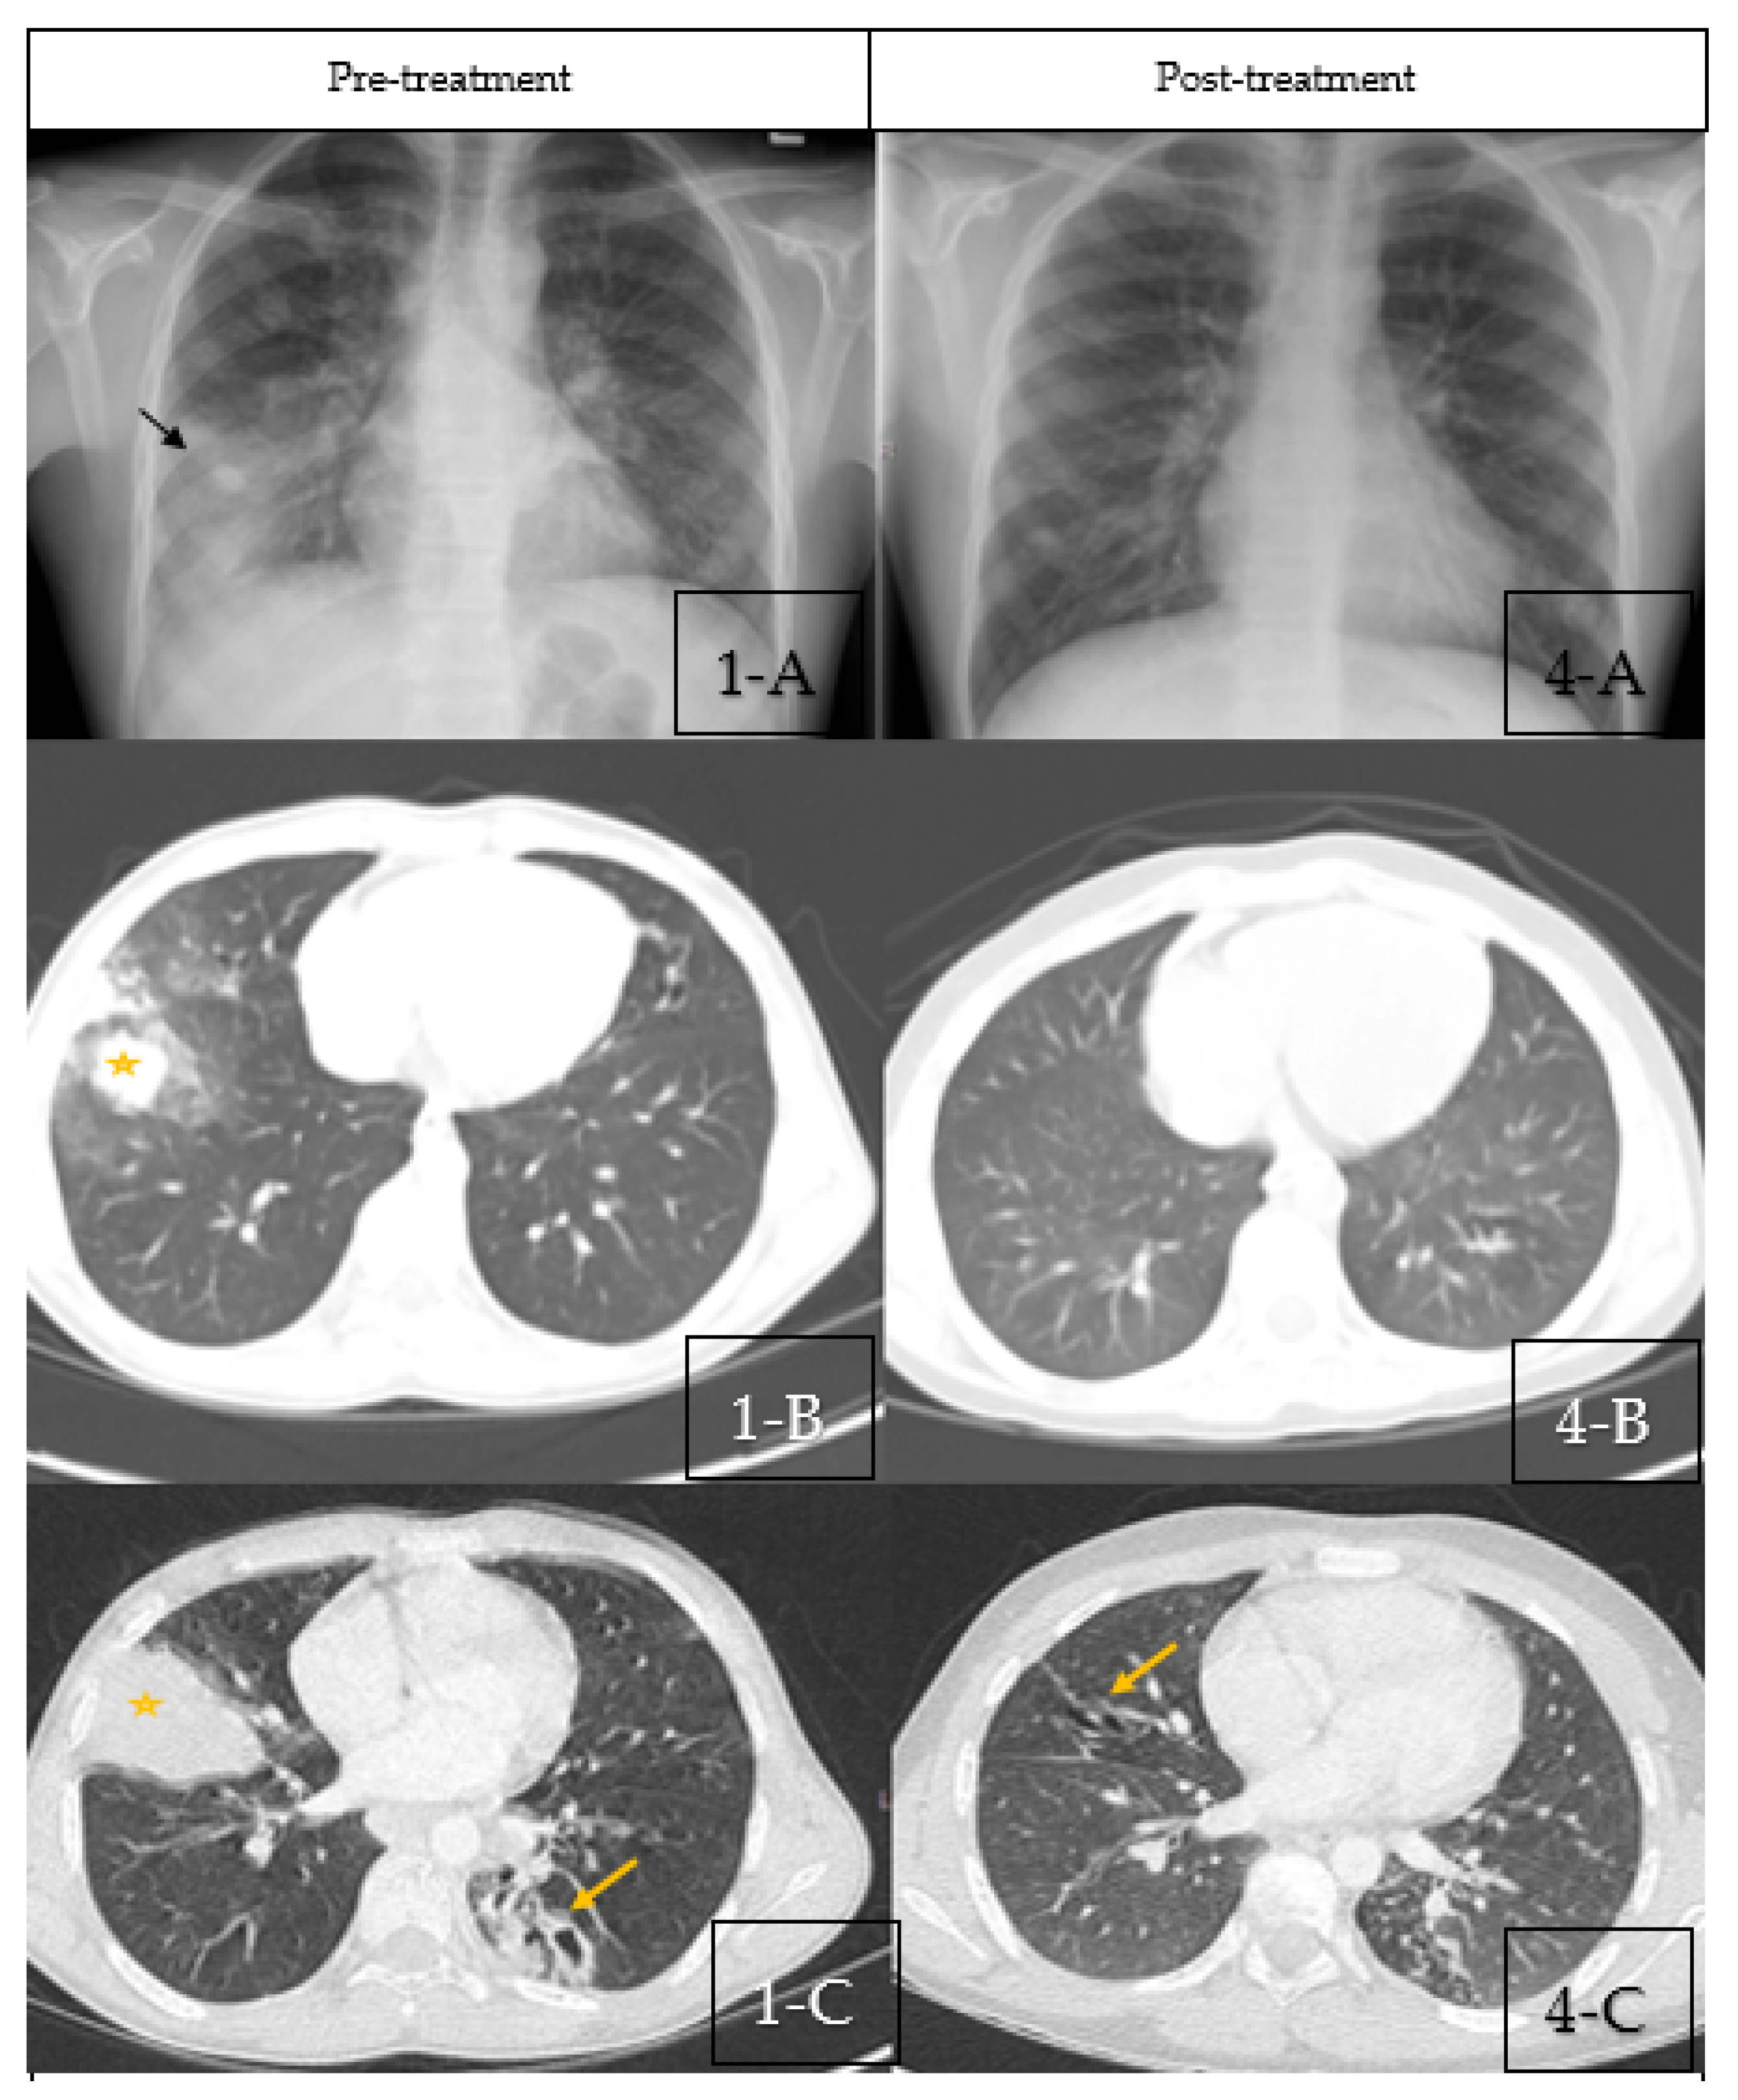

A chest X-ray (CXR) showed right middle lobe consolidation (RML) with bilateral scattered nodular opacities (Figure 1(1-A)). The patient was started on intravenous antibiotics with presumptive diagnosis of bacterial pneumonia. Chest computed tomography (CT) was obtained which showed bilateral central bronchiectasis, mucus impaction and areas of segmental, and sub-segmental atelectasis (Figure 1(1-B,1-C)).

Figure 1.

(1-A–1-C) Pre-treatment Imaging. (1-A): Chest X-ray pre-treatment with pulse steroids showing right middle lobe con-solidation (Black Arrow) with bilateral scattered nodular opacities. (1-B,1-C): Coronal sections of chest CT scan at diagnosis showing bilateral central bronchiectasis, mucus impaction (Yellow Arrow) and areas of segmental, and subsegmental atelectasis (Star). (4-A–4-C) Post-treatment Imaging: (4-A): Chest X-ray post-treatment with pulse steroids showing disappearance of right middle lobe consolidation. (4-B,4-C): Coronal sections of chest CT scan post-treatment with pulse steroids showing resolution of the previous findings with residual bronchiectasis (Yellow arrows).